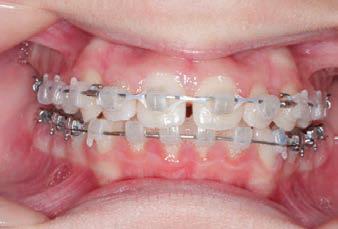

CLASS II DIV.1 - Marra

INITIAL - 4/4/18

PROGRESS 1 - 26/9/18 - Class I platform accomplished in 5.75 months with Motion 3D COLOR Appliance

PROGRESS 2 - 26/9/18 - Placement of the SLX 3D Clear Brackets